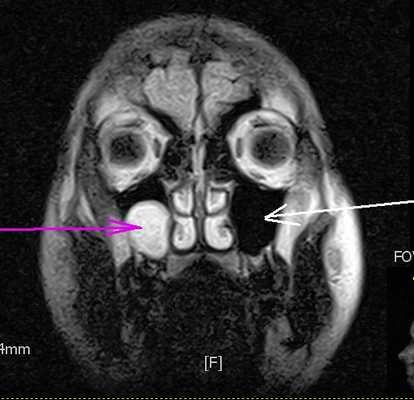

МРТ головного мозга. Т2-взвешенная аксиальная МРТ. Болезнь Маркиафава-Биньями.

МРТ головного мозга. Т2-взвешенная сагиттальная МРТ. Очаг в мозолистом теле при болезни Маркиафава-Биньями тип В.

МРТ головного мозга типа ДВИ. Гиперинтенсивные участки в лобных долях при остром типе болезни Маркиафавы-Биньями.

При энцефалопатии Вернике на Т2-взвешенных МРТ головного мозга симметрично поражаются зрительные бугры, пластина четверохолмия и сосочковые тельца, иногда с участками кровоизлияний.

При МРТ в СПб мы нередко сталкиваемся с характерными изменениями головного мозга в виде гиперинтенсивных очагов на Т2-взвешенных МРТ. При МРТ головного мозга при алкоголизме кроме мозолистого тела и перивентрикулярных зон могут выявляться зоны повреждения коры лобных и височных долей. В острой стадии они хорошо видны на диффузионно-взвешенных МРТ.